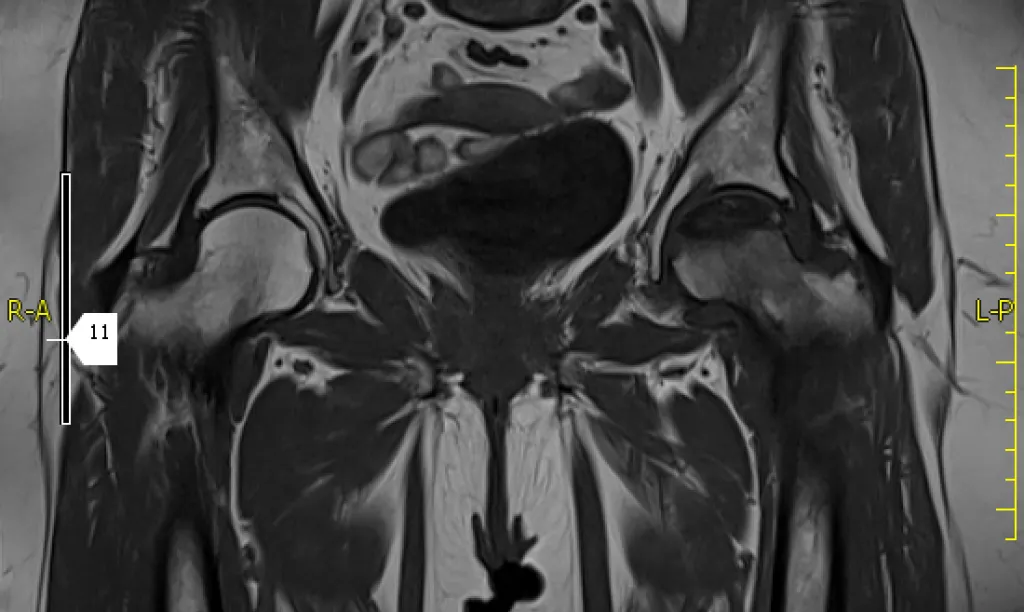

Resonancia magnética 2 regiones anatómicas

La combinación de 2 regiones hace posible el estudio conjunto de caderas y articulación sacroilíaca o valoración de columna dorsal y lumbar.

La resonancia magnética es una prueba irremplazable en la valoración de ciertas áreas anatómicas como el musculoesquelético (rodillas, hombro, caderas…) y neurológicos (columna, cerebral,…).

Se utiliza para todas las áreas del cuerpo y es esencial en musculoesquelético y sistema nervioso.